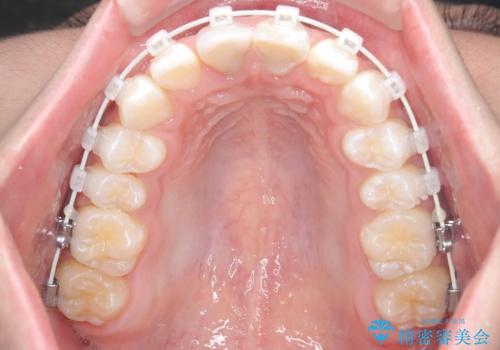

【ワイヤー矯正 11ヵ月で矯正終了!】歯のでこぼこを治したい!

- 「歯のでこぼこを治したい 1年くらいで矯正を終わらせたい」を主訴に来院された患者様です。

叢生量は多く無く歯の傾斜も標準傾斜だったので歯は抜かずにワイヤー矯正で治療を行いました。

左側は2級傾向が強く臼歯の遠心移動をご提案しましたが、1年以内に矯正を終わらせたいという患者様のご意向で希望されず叢生を改善する矯正となりました。